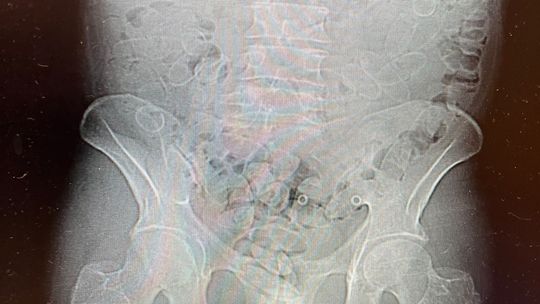

Funkcjonariusze KAS udaremnili przemyt niemal 0,8 kg kokainy na lotnisku w Gdańsku. 40-letni mężczyzna próbował przemycić narkotyki w organizmie – połknął aż 88 kapsułek.